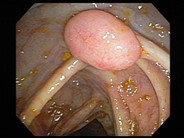

Follicular lymphoma (grade 1/3) in a hepatic flexure polyp - 4.

Author: Julia M. Braza

Category: Lymphoma: Mature B-cell and Plasma cell Neoplasms > Low-grade B-cell lymphoma > Follicular Lymphoma

Published Date: 11/01/2007